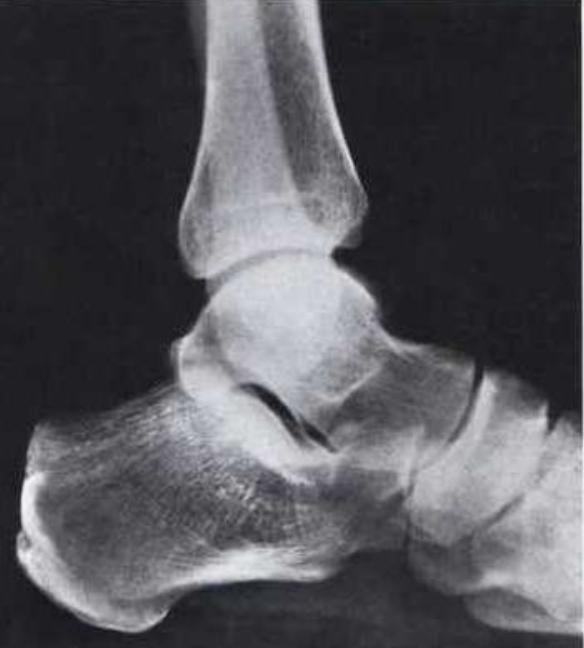

What is this view of the ankle? what views are missing?

Lateral

MISSING:

AP

Oblique